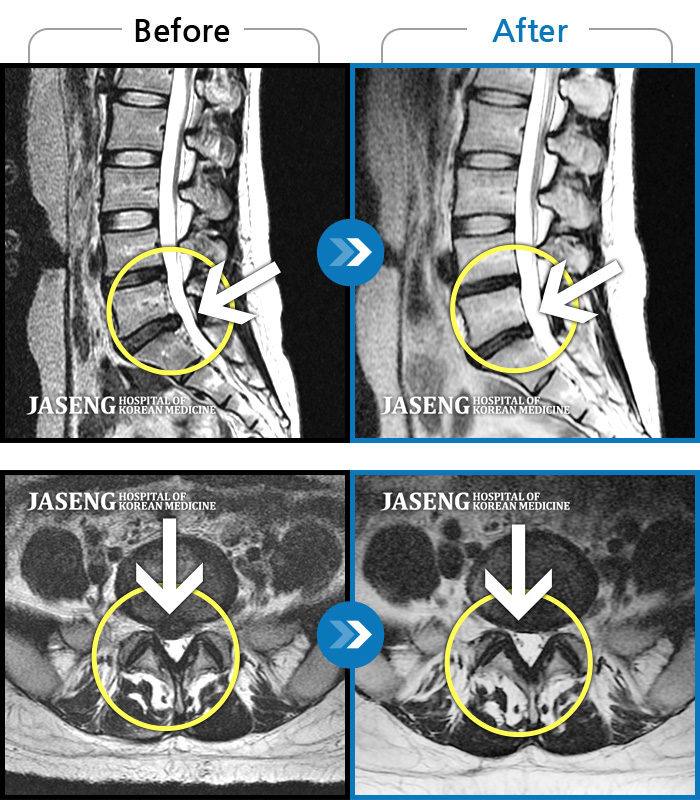

MRI로 보는 치료결과

60건의 MRI 전후 사진으로 터진 디스크 흡수 사례를 확인하세요.

처음 내원시 목에서 등으로 이어지는 통증 및 우측 팔 저림 증상이 심했고, 약간의 근력저하도 동반되어 일상생활이 어려운 상태였습니다. |

[인천] 24.04.06~24.11.16

※ 환자분에게 사전 동의를 받아 동일 조건에서 촬영되었으며, 개인에 따라 치료 후 부작용이 발생할 수도 있으니 사전에 의료진과 상담 후 치료를 진행하시기 바랍니다.